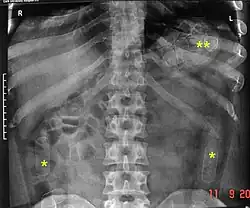

Распространённым способом скрытного транзита наркотиков через границы является его провоз в телах наркокурьеров, в том числе в желудке и кишечнике, особенно при использовании авиалиний и перевозке наиболее дорогих на единицу массы веществ (героин, кокаин)[2]. Формируются небольшие пакеты (несколько граммов), упакованные в герметичную тару, например презервативы, которые затем проглатываются. Курьер может везти до десятков таких пакетов. Если пакет разрывается или теряет герметичность, курьер, как правило, погибает от передозировки наркотика[4]. Через 2—3 суток пакеты выходят естественным путём вместе с калом. В случае необходимости быстрого извлечения пакетов курьеру дается сильное слабительное.